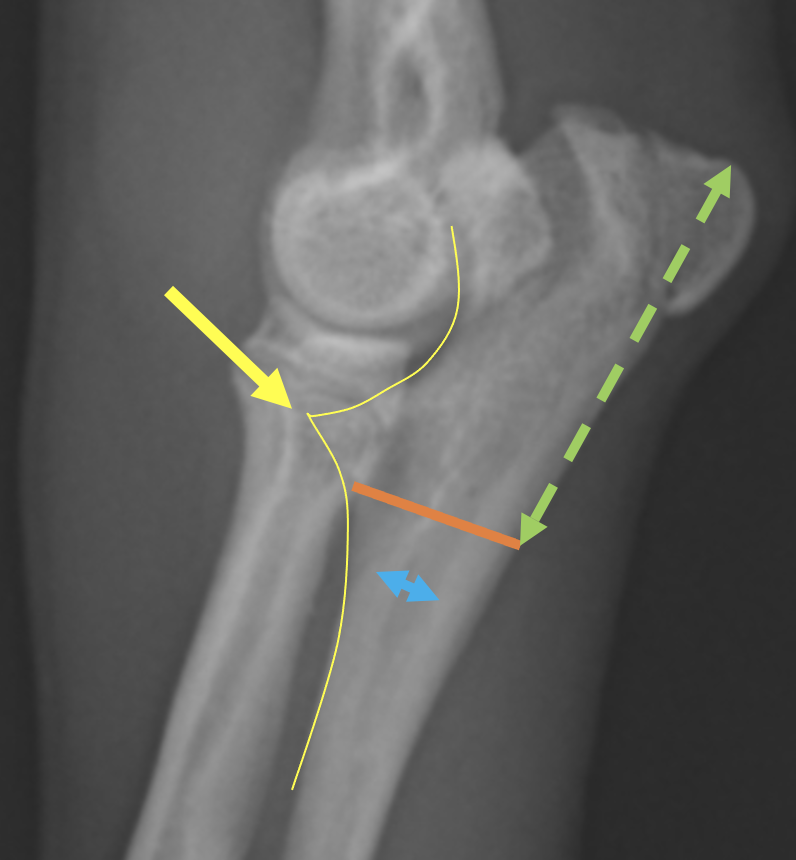

成長板を治すことは不可能なので、短い尺骨を伸ばし、少しでも肘の関節をもとに戻すことが目的となります。

骨を切断して、伸ばしていくわけですが、どこを切っても良いわけではなく、なるべく関節に近いところで、関節内でないところを切断します。この画像のオレンジの部分で切断することとなります。それにより肘が伸びて上に移動することが予想されます。切りっぱなしにすることもありますが、髄内ピンを入れておくことである程度の安定性をもたせることができ、術後早期の歩行が可能となります。髄腔が非常に狭く8mmほどしかなかったため、8mmのピンを使用しました。